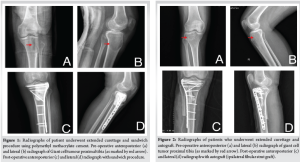

The average age of the patients in the study was 35.69 ± 12.75 years (range: 18–69 years). There were 18 men and 13 women. The distal femur were 12 and proximal tibia were 19 involved in our study. 29 patients had a primary GCT while 2 patients had a recurrent GCT. The tumors were staged radiologically using the Campanacci grading. There were eleven cases of Grade II tumor and twenty cases of Grade III tumor. Five patients had pathological fracture at presentation. In our study, 6 underwent the sandwich procedure using PMMA as a void filler (Fig. 1), 10 underwent extended curettage and autologous bone graft (Fig. 2), 11 underwent extended curettage and morselized allograft (Fig. 3), and 4 patients underwent endoprosthesis (Fig. 4).

The aim of this study was to evaluate the clinical and radiological outcomes in patients with GCTs around the knee who underwent surgical treatment, with a minimum follow-up period of 1 year. GCT is a benign primary bone tumor that is locally aggressive but has the potential for malignant metastasis [3-7]. It accounts for 5–7% of all primary bone tumors and approximately 20% of benign bone tumors [8]. Typically, GCTs occur in the epiphyseal-metaphyseal regions of long bones and predominantly affect individuals aged 20–40 years. Our study included 31 patients with GCTs around the knee. Of these, 19 patients (61%) had tumors in the proximal tibia, while 12 patients (39%) had tumors in the distal femur. A significant proportion, 20 patients (64.5%), fell within the 20–40 age group. As per to literature, it has shown more female preponderance than male [9]. Our study had involved 18 males (58%) making it greater than females in the study period, but it was statistically not significant. GCT can present with a vast variety of symptoms, for example, pain, swelling, decreased joint mobility, fracture of involved bone, neurovascular involvement of the limb, or accidental finding while routine check-up. Most of the patients enrolled in our study presented with above above-listed complaints but 5 (16.12%) of 31 patients presented with pathological fracture around knee. Evaluation for GCT involves non-invasive and invasive modalities. Initial radiographs and MRI are usually performed where it appears as a pure lytic cystic lesion that frequently, though not always, grows eccentrically in the epiphysio-metaphyseal area of the bone. The bone’s afflicted region may enlarge, while the cortical bone may become thinner. In an advanced stage, the GCT breaks through the cortex, and the production of spicules around the tumour occurs in the absence of periosteal response [5]. The MRI indicators of GCT include evidence of tissue haemorrhages, high contrast medium enhancement, and high signal intensity in T2-weighted images [10]. As per the description given for GCT [11], 11 (35.48%) patients belonged to grade II, and 20 (64.52%) patients were of grade III in our conducted study. Systematic analysis of existing literature suggests that Campanacci Grade III GCTs are commonly associated with pathological fractures at presentation [12]. Of the 5 pathological fractures in our study, all belonged to Campanacci grade III. Extended curettage has been used to treat GCT for a long time [6]. The tumor can be removed either by broad excision or curettage with or without local adjuvants depending on the involvement of the articular surfaces. In one of our previous published study of synchronous GCT around talus, we have performed extended curettage and allograft to treat the bone defect and provide mechanical stability and there was no local recurrence of tumor or altered joint functionality [13]. However, the question of restoring bone abnormalities has been divisive ever since. Several studies have shown that bone cement or bone transplants can be used to treat a bone deficit. There are currently no high-quality comparison studies in the literature that expressly assess the GCT around the knee joint and include a specific Campanacci grading. In our study, 7 patients underwent extended curettage and bone grafting, 6 patients underwent wide excision and endoprosthesis. Of the 25 patients for bone defect after curettage, 12 patients underwent sandwich procedure, 7 underwent wide excision and autograft from iliac crest or iliac crest and fibular strut and 6 underwent bone cement. Bone cement as an adjuvant with bone graft was used in all the extended curettage patients for deficit bone. The use of bone cement as an adjuvant reduced the local recurrence rate in individuals who had curettage to 12–27% [14]. The result of a methodical effort to reduce recurrence rates is the use of a wide variety of adjuvants after curettage, such as the local application of phenol, PMMA, liquid nitrogen, or a combination of many choices. Probably, the most well-established treatment to employ after curettage is phenol and PMMA. In our study, we included only primary or recurrent GCTs belonging to grade II or III and reported local recurrence only in 1 patient who underwent sandwich procedure after 1 year of follow-up. Post-operative infection is one of the common complications noted in most of the surgeries. Here, in case of GCTs around knee, infection rate is compared between intralesional curettage and wide excision studies conducted in past [6]. They reported an infection rate of 5.8%. A systematic analysis that included one of the largest series of wide resections for GCTs reported an infection rate of 6.3% [12]. We reported no infection around knee in our study. The need for revision surgery is needed in case of local recurrence, infection, or implant-related complications. A systematic analysis [12] reported that revision surgeries were frequently required following endoprosthesis, with rates exceeding 40% in some series. In our retrospective study, there was no revision surgery needed. The MSTS rating scores reported in the various series frequently represented exceptional or excellent functional results [12]. In our study, MSTS mean was 28.91 for sandwich procedure, 29.28 for extended curettage and bone graft, 26.33 for extended curettage and bone cement, and 27.83 for endoprosthesis.